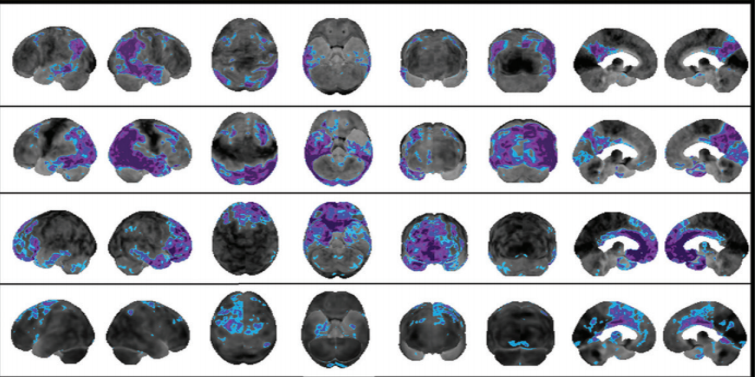

Alzheimer disease

frontotemporal dementia

lewy body dementia

corticobasal degeneration